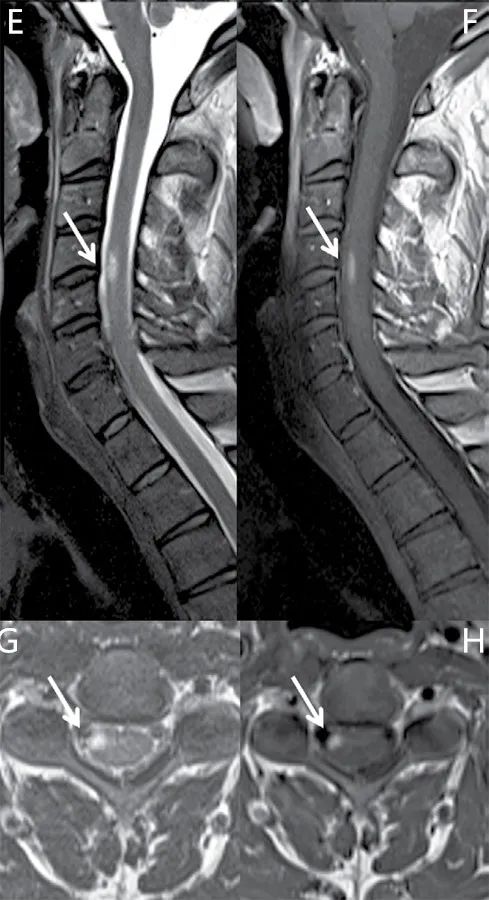

脑MRI通常表现为特征性部位的多灶性T2高信号脑白质病变,包括脑室周围(含胼胝体)、近皮层区域(毗邻大脑皮层)、幕下区域。在T1加权像上,病变可能出现低信号的表现(即所谓的“黑洞”)。脊髓损伤则发生在80%~90%的MS患者和一半的CIS患者,最常见于颈椎。病变延伸超过一个或两个椎骨段,并且经常偏离中心,邻接软膜表面。脑和脊髓的病变在钆增强扫描后可能强化(图)。

图1 MS的典型脑和脊髓病变(箭头显示病变位置) A、B:轴位MRI扫描显示脑室周围多发病变,其中一个病灶增强扫描可见强化;C:显示近皮层区域病变;D:显示幕下病变;E、F、G、H:矢状位和轴位扫描显示颈髓病变,增强扫描可见强化。